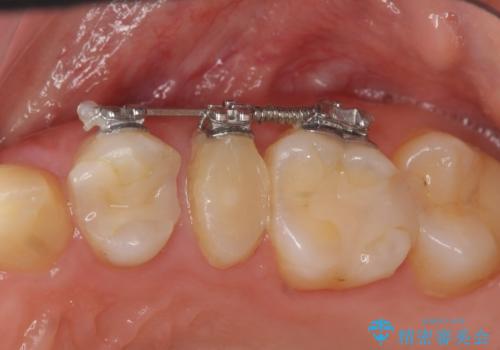

挺出小矯正を行った縁下カリエス治療

X線撮影を行い、隣接面に多発した虫歯と歯ぐきよりも深くなってしまった虫歯を小矯正をおこなったのちのセラミック治療で問題を解決します。

小矯正を行い深い虫歯を改善した後は、小手術を行うことで歯ぐき・周囲歯槽骨の状態を整えることでより安定した歯周環境を得ることができます。